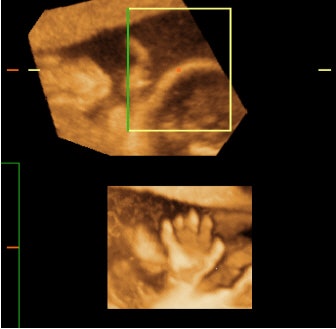

![]() |

| Figure 4, a comparison between 2-D and 3-D representations of a fetal hand. Upper image: A traditional 2-D ultrasound image of a fetal hand, which, without an explanation is difficult for the parents-to-be to comprehend. Lower image: A 3-D ultrasound photographic- style image of the same fetal hand, which is much more easily recognized and appreciated by the parents-to-be. Images courtesy of Dr. Stefano Ciatti. |

The clarity of these 3-D pictures dramatically demonstrate the concrete reality of the pregnancy and the developing baby to the parents-to-be. The fact that these pictures are 3-D representations of the fetus, and therefore similar to all of our 3-D representations in life, allows almost anyone to appreciate and understand what they are looking at very quickly, unlike traditional ultrasound pictures.